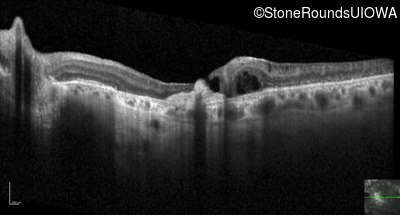

Optical Coherence Tomography - Left - 20/80

Exemplar / OCT Stack